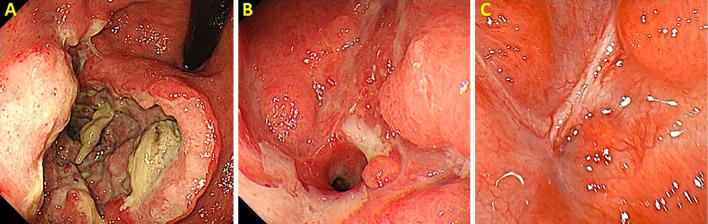

We herein report a 79-year-old man diagnosed with primary gastric diffuse large B-cell lymphoma (DLBCL) with gastropleural fistula (GPF), successfully treated by chemotherapy without surgery. If primary gastric DLBCL perforates during chemotherapy, surgery is often warranted. Our patient's computed tomography findings showed loculated pleural effusion with air foci in the left lower lobe, suggesting GPF. After six cycles of rituximab, cyclophosphamide, doxorubicin, vincristine, and prednisone (R-CHOP) chemotherapy, the fistula fully closed, and complete remission was achieved. In conclusion, while gastric DLBCL can exhibit spontaneous GPF, it can be treated with chemotherapy alone, which was well-tolerated in our patient.

我们在此报告一例 79 岁男性,诊断为原发性胃弥漫性大 B 细胞淋巴瘤(DLBCL)合并胃-胸膜瘘(GPF),经化疗而非手术成功治疗。如果原发性胃 DLBCL 在化疗过程中穿孔,通常需要手术。我们患者的 CT 检查结果显示左侧下叶有分隔性胸腔积液并伴有气腔,提示存在 GPF。在接受六周期利妥昔单抗、环磷酰胺、多柔比星、长春新碱和泼尼松(R-CHOP)化疗后,瘘完全闭合,达到完全缓解。总之,虽然胃 DLBCL 可自发出现 GPF,但可单独采用化疗治疗,我们的患者对此治疗耐受良好。